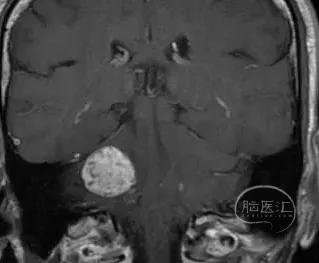

核磁共振检查发现右侧桥小脑角区占位

肿瘤最大直径约2.6 cm

术前影像

术前影像资料

(肿瘤长入内听道内较深-9.1mm)

术前内听道扩大(右侧)

术前影像资料

肿瘤长入内听道内较深-10.3mm

肿瘤压迫脑干